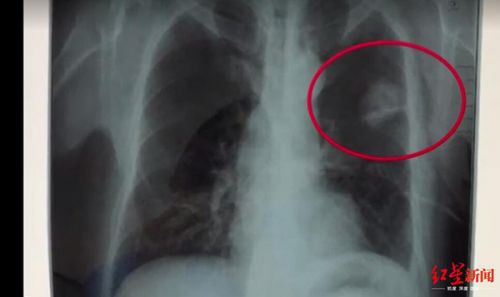

體檢胸片顯示的陰影

2018年5月7日,法院公開開庭審理了此案。四川勞研科技有限公司代理人在庭審中辯稱,陳志鵬體檢當(dāng)天,初審醫(yī)生在查看其胸片的時(shí)候,發(fā)現(xiàn)陳志鵬左上肺有陰影,將該情況記錄在案,并且在體檢當(dāng)天電話告知陳志鵬本人,詢問其是否出現(xiàn)癥狀,并且建議其復(fù)查。但陳志鵬說,他沒有聽到醫(yī)生要求摘掉自己所佩戴的玉佩,肺部的陰影應(yīng)該是玉佩所留,并且表示自己身體沒有出現(xiàn)任何不適癥狀。

在最終出具體檢報(bào)告前,體檢醫(yī)生再次致電陳志鵬,要求其進(jìn)行復(fù)查,但是他依然提出不用復(fù)查。在法庭上,檢查陳志鵬胸片的醫(yī)師出庭,法官對她進(jìn)行了詢問,該女醫(yī)師稱,“就是他(陳志鵬)一直說戴了一個(gè)玉佩,正常說來玉佩在胸片上,會(huì)顯示有陰影的,不可能就消失了,然后再問他癥狀,他說什么癥狀都沒得,也不咳嗽,也不胸悶,他說正常的很,然后我們結(jié)合這些癥狀和胸片的情況,就出具了未見明顯異常的報(bào)告。”